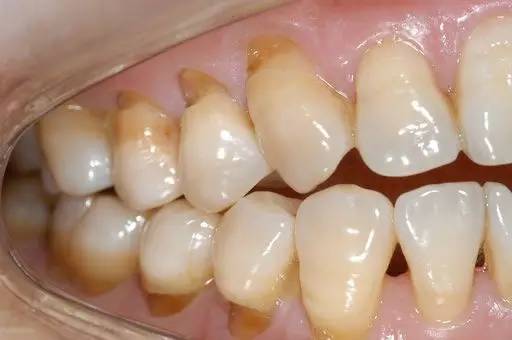

很多人觉得刷牙只不过是一件小事情,其实不然。现在,请你先对照镜子,张开嘴,看看你的牙齿根部,是不是像下图一样,隐隐约约有些凹下去了?如果是,那你就得当心了!

与普通蛀牙不同,出现这种情况,你的牙齿危险了!医学上称之为“楔状缺损”!

这种横槽就是“楔状缺失”!由于它外形酷似木匠用的楔子,因此称为“楔状缺损”。

楔状缺损是发生在牙齿唇、颊面颈部的慢性硬组织缺损,呈“V”状,由于它的外形酷似木匠用的楔子,因而得名楔状缺损。多见于前牙或者双尖牙的唇面,以中老年患者居多。